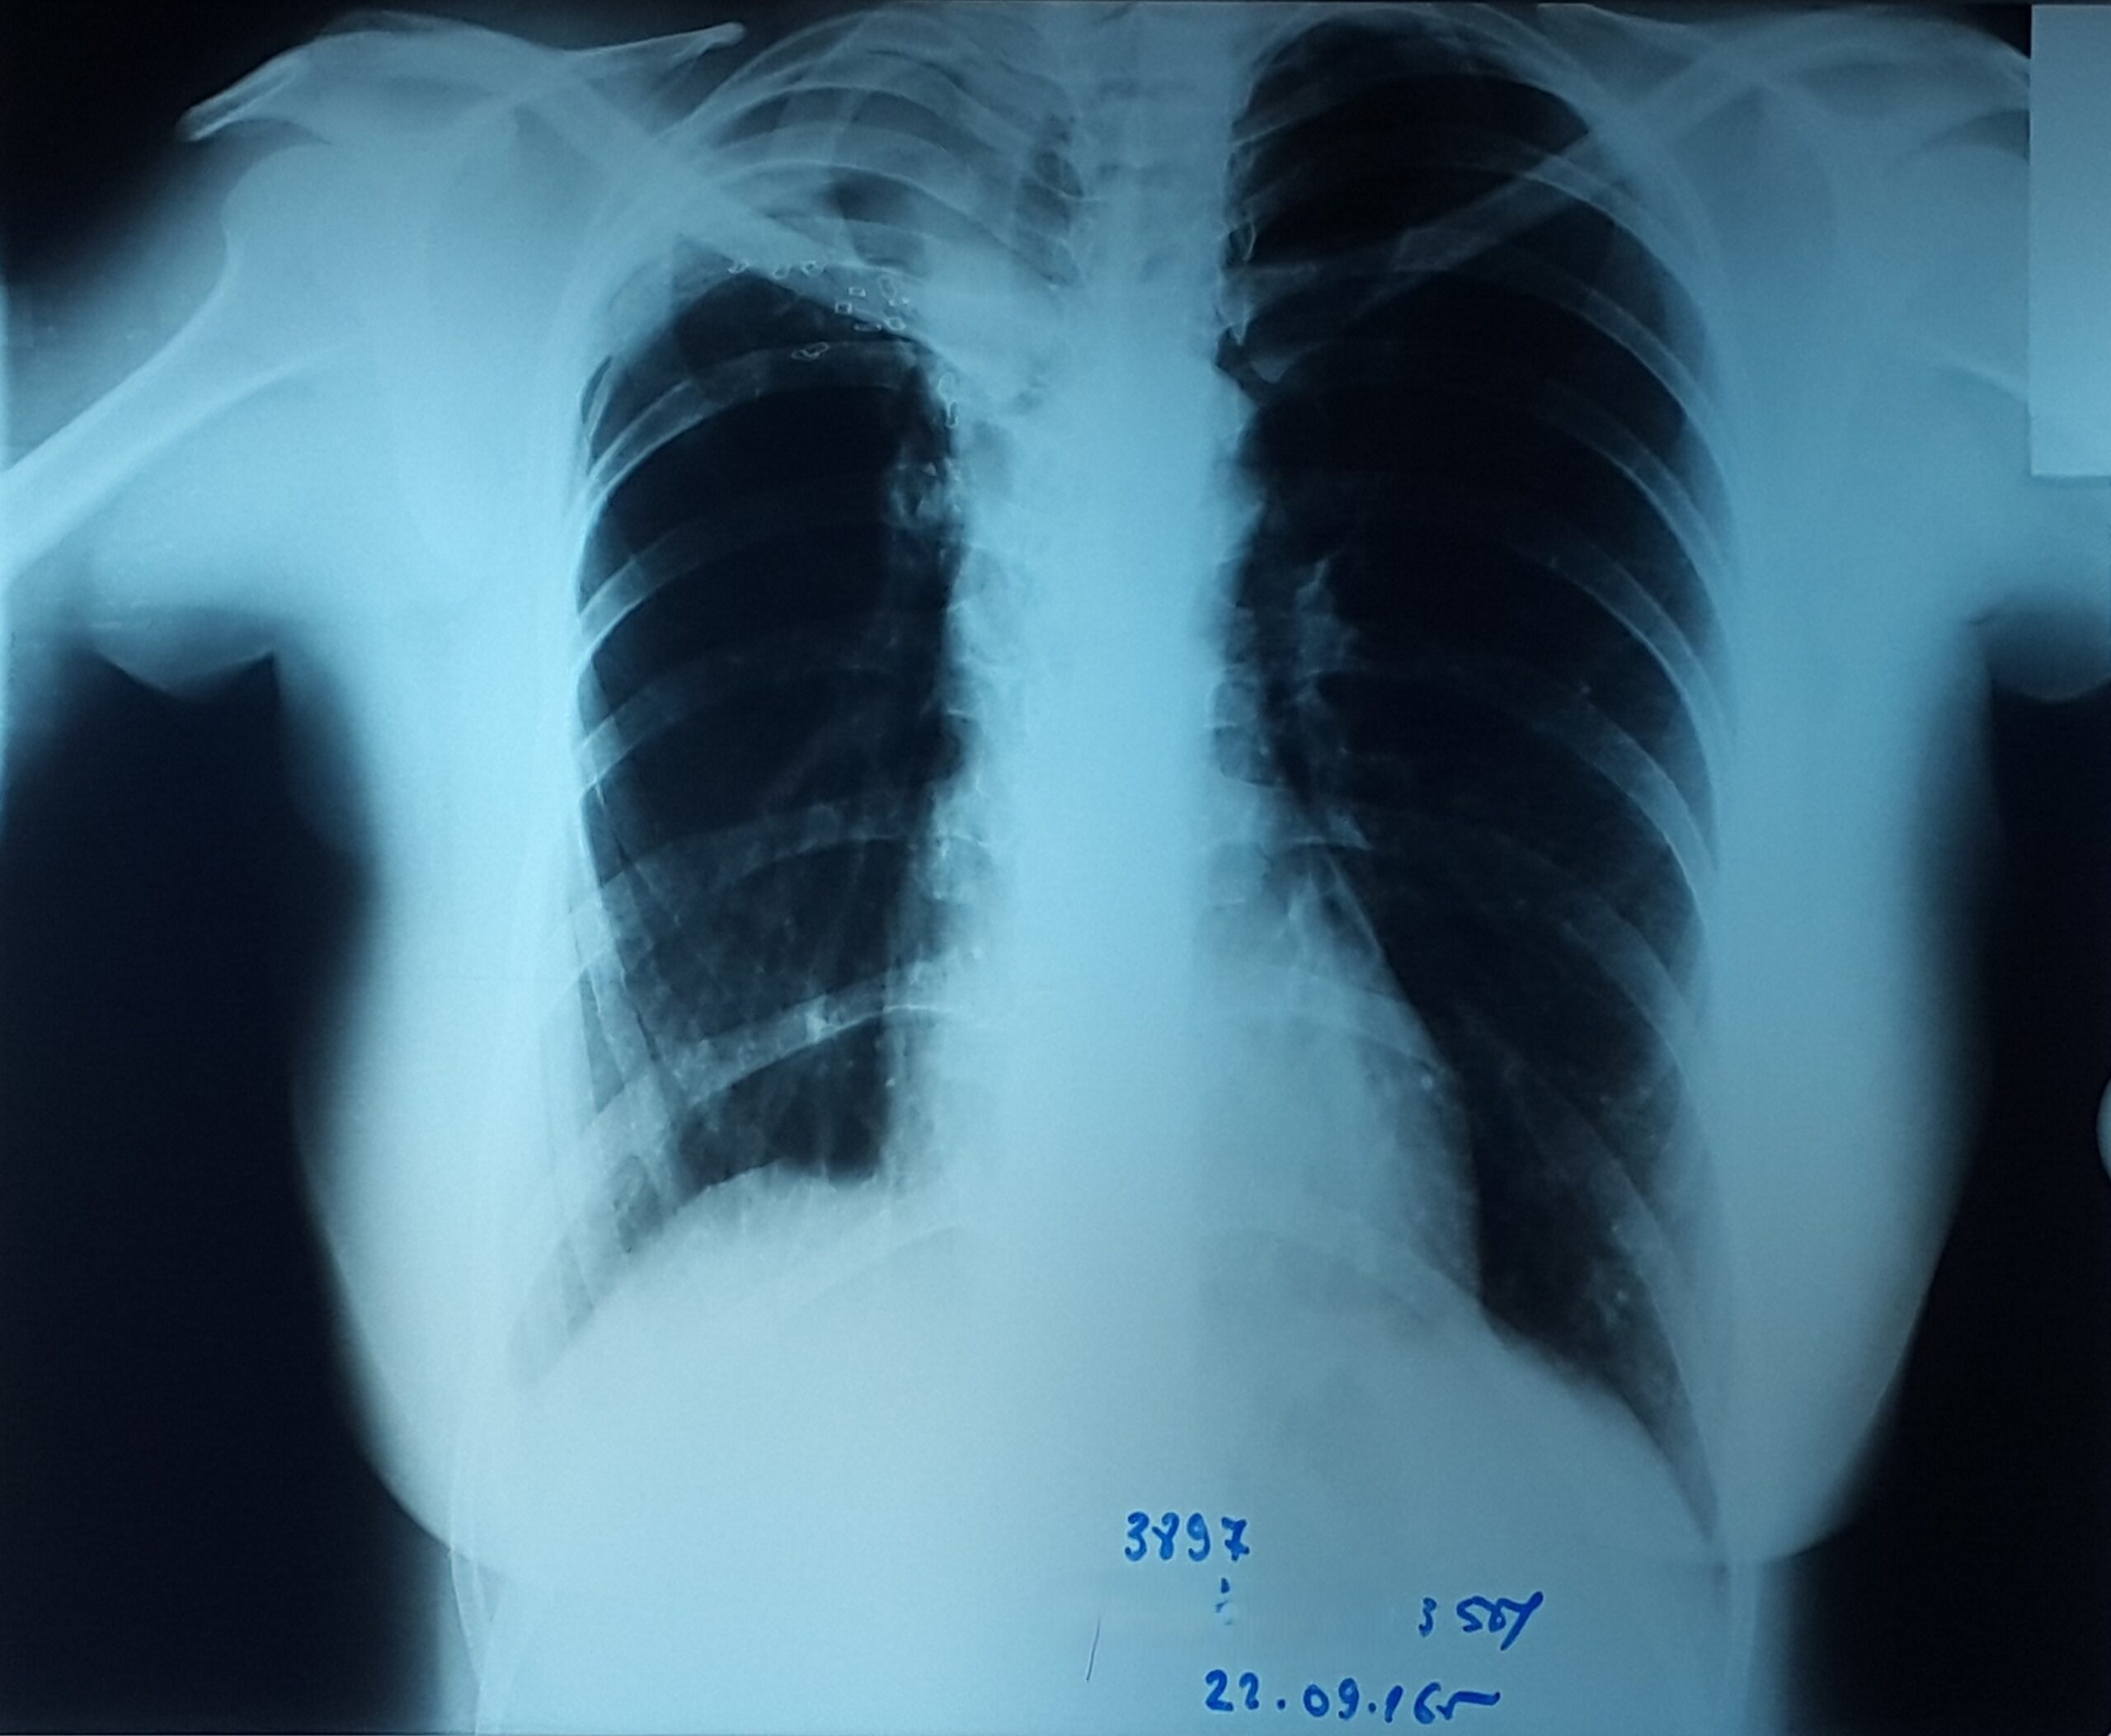

პაციენტი 37 წლის ქალი. 1997 წ-ს გაკეთებული აქვს მარჯვენა ზედა წილის რეზექცია ფილტვის ტუბერკულოზის გამო. წლების განმავლობაში აქვს გამწვავებები, რაც გამოიხატება მაღალი ცხელებით, ხველით, დიდი რაოდენობით სისხლნარევი, მძაფრი სუნის მქონე ნახველის გამოყოფით. რენტგენოლოგიურად ინახა დიდი ზომის ღრუ მარჯვენა ფილტვის ზედა ველში. ბრონქოსკოპიით ინახა დიდი ზომის მარჯვენა ზ/წილოვანი ბრონქის ტაკვის ფისტულა. ტაკვის სიგრძე იძლეოდა ბლოკატორის ჩადგმის შესაძლებლობას. რიგიდული ბრონქოსკოპით მარჯვენა ზ/წილოვან ბრონქში ჩაიდგა MEDLUNG-ის ბლოკატორი N13. რამოდენიმე საათში საჭირო გახდა ბლოკატორის გამოცვლა ნაკლებ (N12) ზომაზე განვითარებული მარჯვენა ქვედა წილის ატელექტაზის გამო. მანიპულაციის შემდეგ პაციენტს შეუწყდა სისხლნარევი და ჩირქოვანი სეკრეტი. 10 თვის შემდეგ საკონტროლო გამოკვლევით ღრუს ადგილას დაფიქსირდა ფიბროთორაქსი. უახლოეს მომავალში, გულმკერდის კტ კვლევის შემდეგ, იგეგმება ბლოკატორის ამოღება.